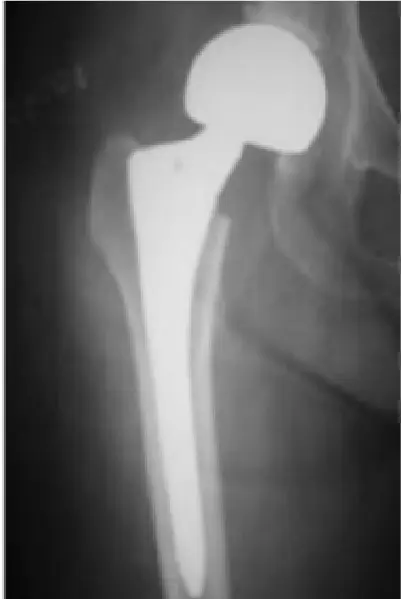

全国の病院では、大腿骨骨折の手術までに平均4〜5日かかるのが現状です。当院では原則48時間以内の手術を目標とし、万全の体制を整えています。大腿骨骨折は「治療の早さ」が回復を左右する重要な疾患だからこそ、これほど手厚く手術室を確保し、患者さんの一日も早い回復を支えます。